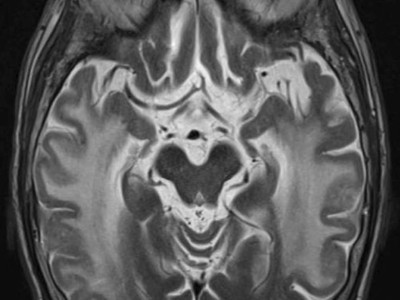

Seit zehn Jahren lagen die Blutdruckwerte einer 58-Jährigen bei über 200/120 mmHg – ohne Beschwerden. Vor drei Monaten kam es plötzlich zu einer transitorischen ischämischen Attacke. Ein Blick in die Anamnese ergab: Vor 30 Jahren musste ihr Kind in der 33. Schwangerschaftswoche wegen Komplikationen geholt werden. Was verbindet dieses Ereignis mit den aktuellen Beschwerden?

Bildnachweise